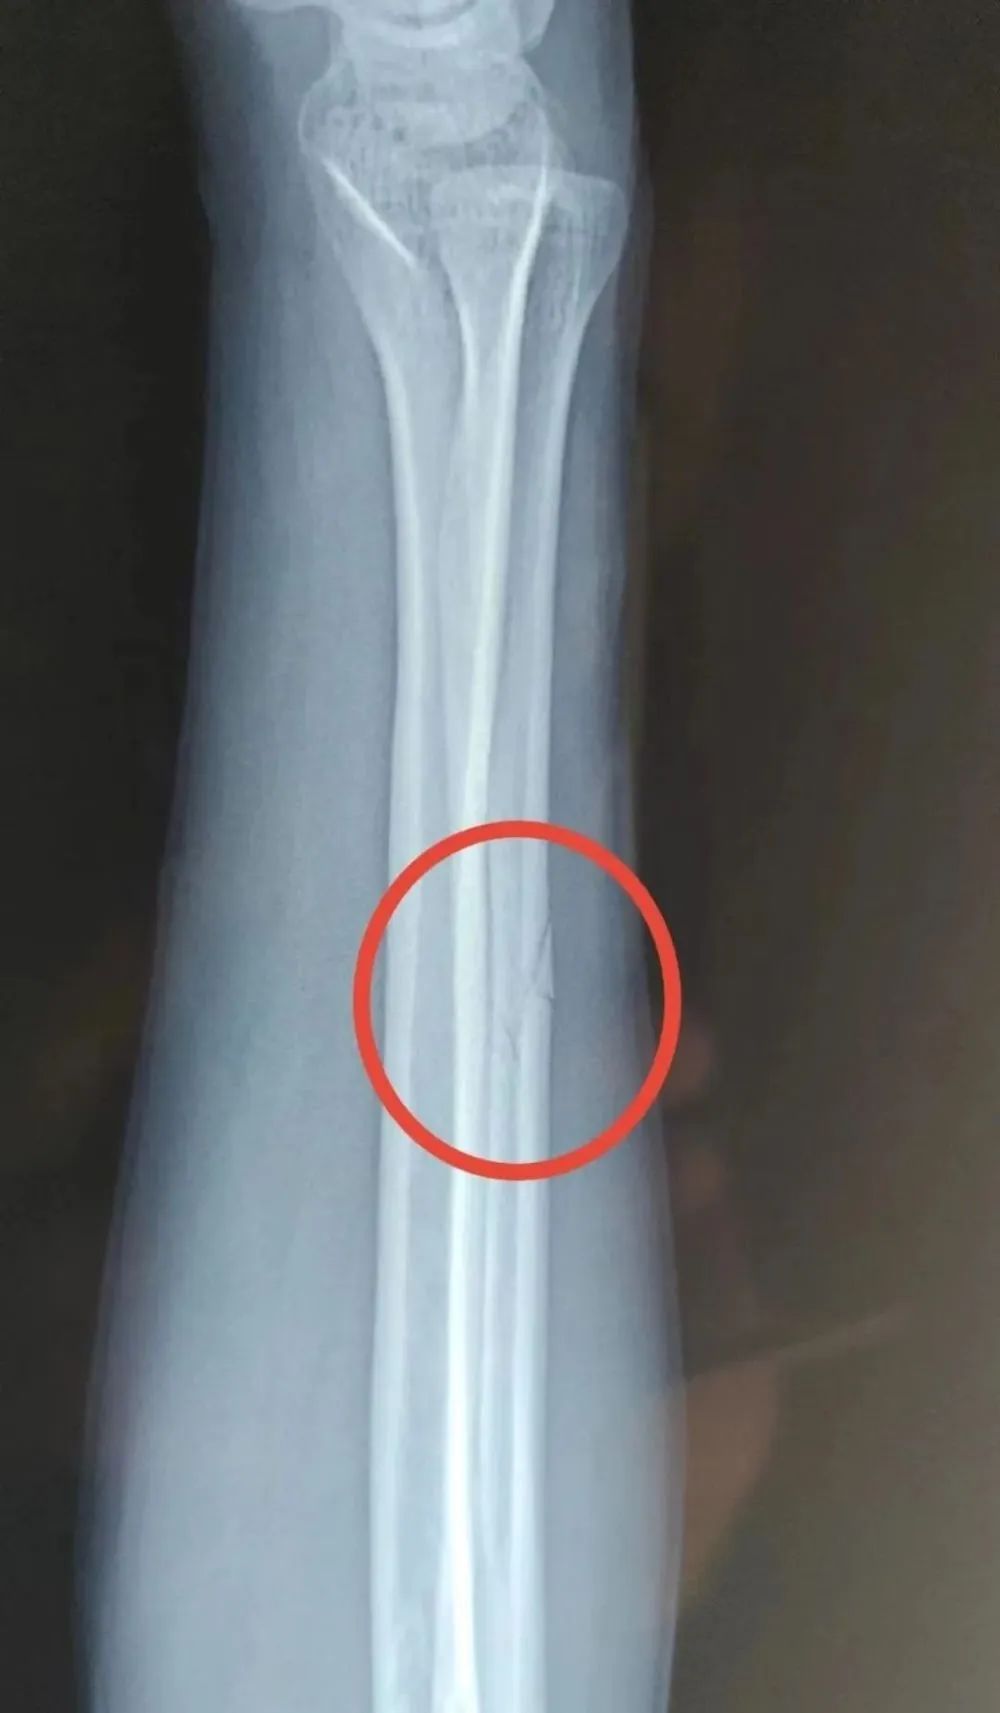

事發(fā)后宋某報(bào)了警,當(dāng)晚去醫(yī)院檢查,打了石膏后,醫(yī)生讓先回家觀察觀察。宋某第二天右臂疼痛難忍,于11月13日18時(shí)自行前往丹鳳縣醫(yī)院檢查,被診斷為右尺骨骨折,外傷性頭疼。

宋某家屬并不認(rèn)可“輕傷二級(jí)”的鑒定結(jié)果,申請(qǐng)重新鑒定。4月18日,宋某拿到了鑒定意見通知書,通知書顯示,宋某人體損傷程度屬于輕傷一級(jí)。

距離事發(fā)已經(jīng)過去了9個(gè)月,宋某第一次傷情鑒定輕傷二級(jí),第二次鑒定輕傷一級(jí),如今還要做第三次鑒定。